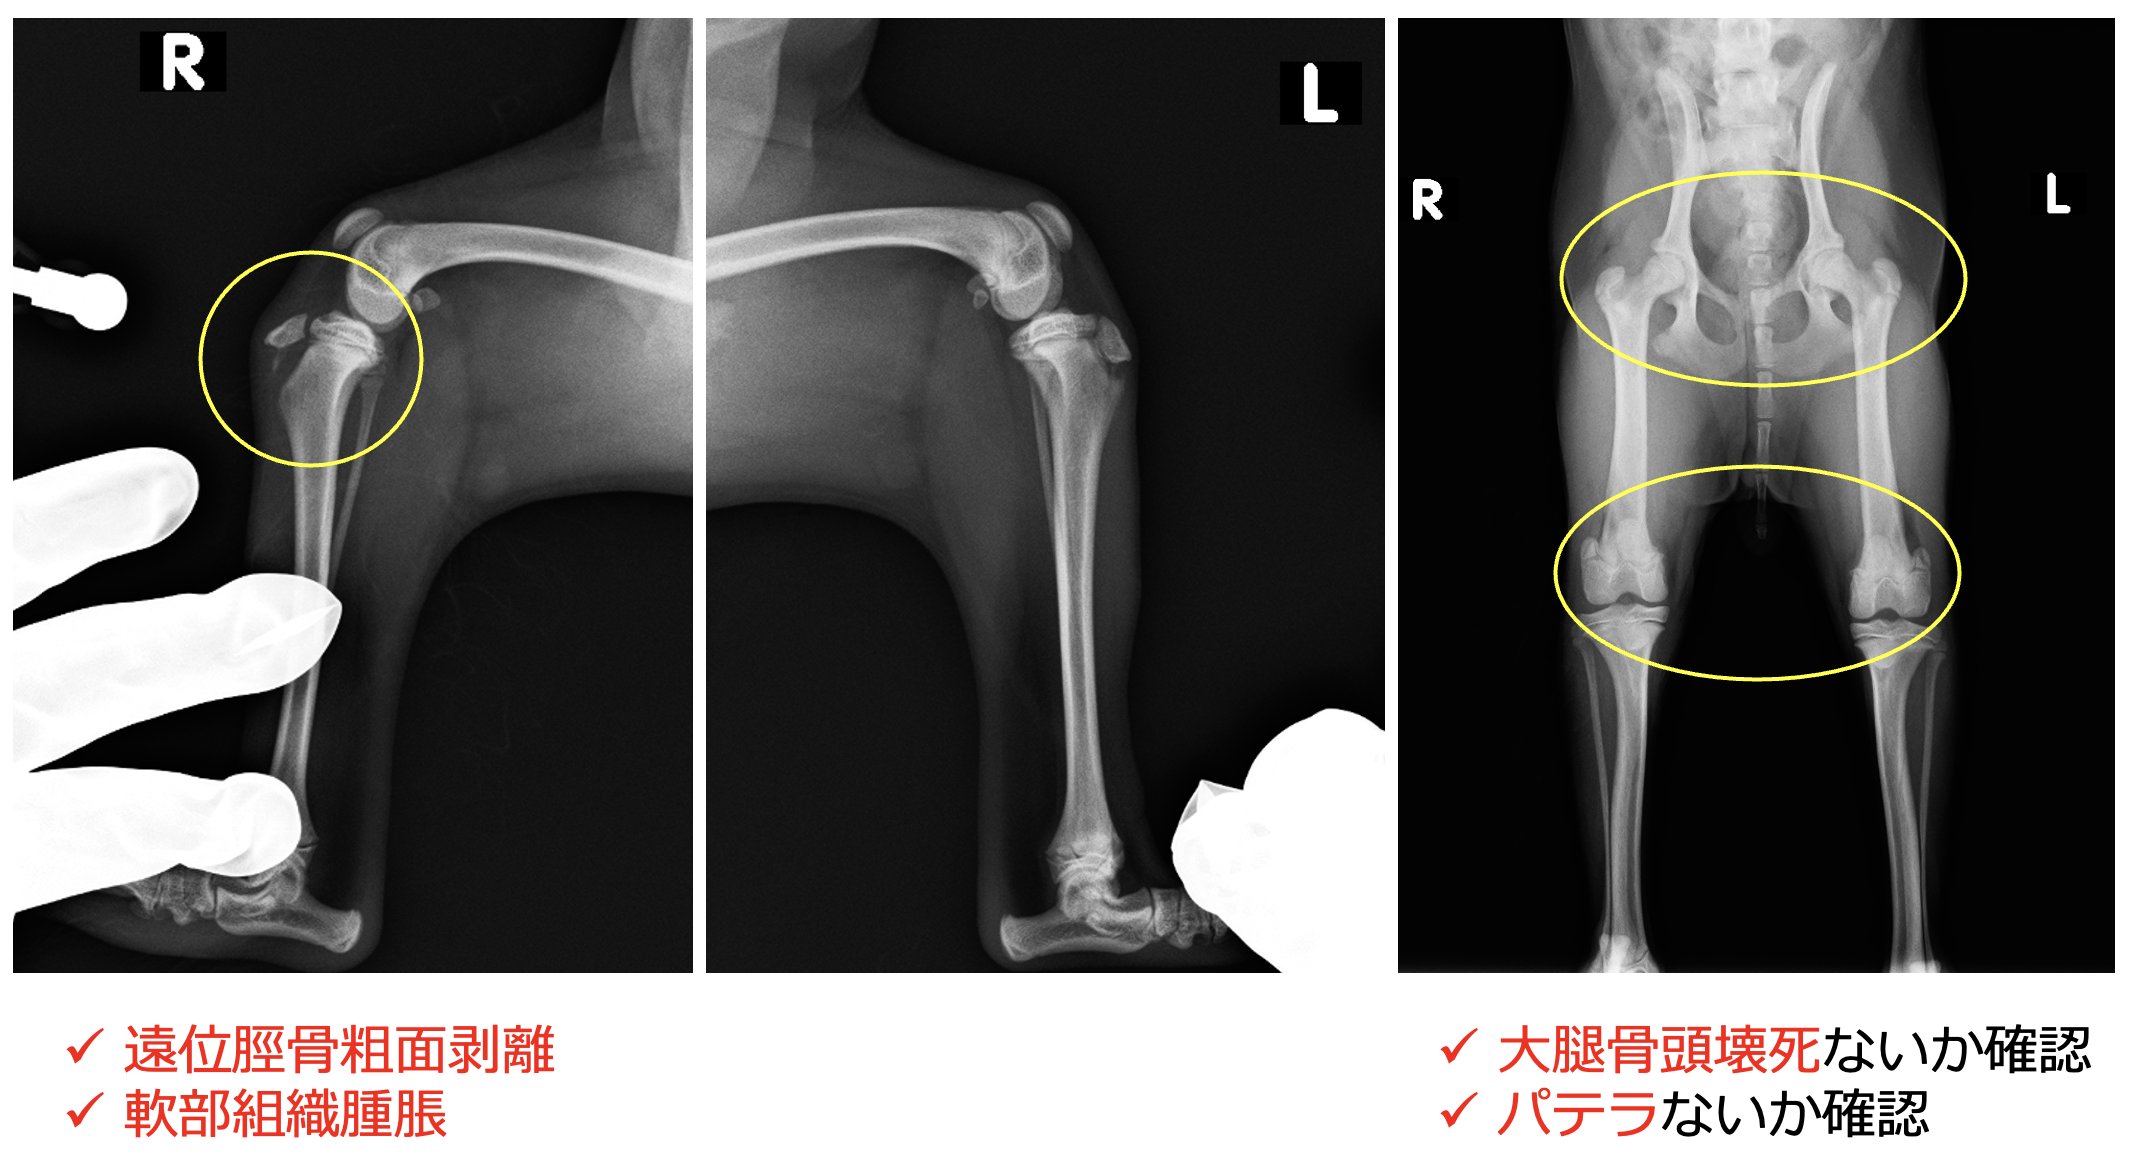

脛骨粗面成長板骨折